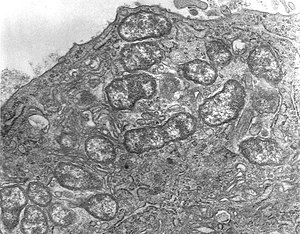

a-c) Transmission electron micrographs of outer membrane vesicles of O tsutsugamushi.

The cellular infection cycle of O. tsutsugamushi[17].

Orientia tsutsugamushi initially attacks the myelocytes in the area of inoculation, and then the endothelial cells lining the vasculature. In the blood circulation, it targets professional phagocytes such as dendritic cells and macrophages in all organs as the secondary targets. The parasite first attaches itself to the target cells using surface proteoglycans present on the host cell and bacterial surface proteins such as type specific protein 56 or type specific antigen, TSA56 and surface cell antigens ScaA and ScaC, which are membrane transporter proteins.[18][19]

These proteins interact with the host fibronectin to induce phagocytosis (the process of ingesting the bacterium). The ability to actually enter the host cell depends on integrin-mediated signaling and reorganisation of the actin cytoskeleton.[20]